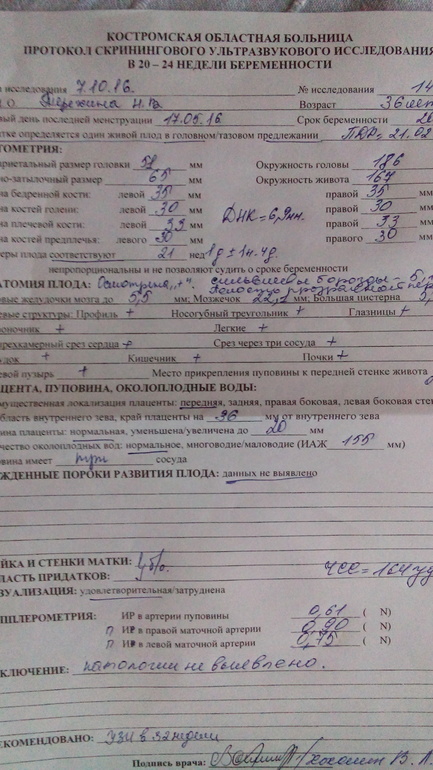

Фото пузиковвсё хорошо, я очень рада! съездила на узи удачно ! и у нас 100% мальчишка! моя интуиция меня не подвела :)))